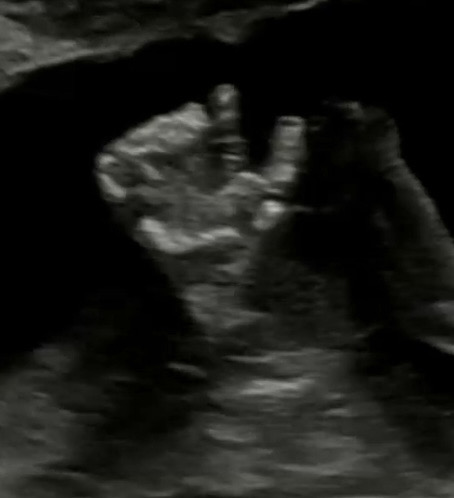

뻔치펀치 아기

얼마 전에 24주5일 첫 임당검사를 했어용 사실 임당검사는 둘째치고 애기가 너무 보고싶었던게 22-24주 들어서니 태동이 꾸물꾸우물 아주 요란하고 앉아 있음 자세가 불편한지 안에서 요동치고 ㅋㅋㅋㅋ 배꼽도 쳐주고 옆으로 누우면 옆구리도 쳐주고 그래서 내가 동네북이지 뭐 하고 초음파 보러가기 전까지 기대 안했는데 초음파 보러갈 때되니 얼마나 컸을지 뭐하고 있을지 너무 궁금하더라구요 가서 보자마자 양수 양도 좋고 태반 위치도 좋고 애기 자세도 좋고 (이제 머리가 아래로 가 있더라구요) 그러면서 주먹 쥔게 보이길래 그걸 확대해주시는데 갑자기 그걸 아래로 슥 빼더니 훅 하고 태반을 치대요 콩 톡 도 아니 툭! 선생님이 엄마 때리네 하시고 간호사님도 발로 그러는건 봤어도 저렇게 세게 엄마 주멍으로 치는건 처음 보신다고 ㅋㅋㅋㅋㅋ ㅠ 그러더니 그 소릴 듣고 힘을 입었는지 한대 더 여유를 두고 치대요... 너무 귀여웠어요 ㅠㅠㅠㅠ 우리 집 새끼라 그런거겠죠 전에 초음파 볼 때 아빠가 콧대가 낮은거냐 할 때도 선생님이 콧대 보여주면서 안낮다 이거봐라 하고 확대해주시는데 그때 슥 코를 만지더니 다 듣나봐여.... 1주 머리 몸통 작고 다리는 2주 길대서 집안에 롱다리 유전자를 눈 씻고 찾아도 없는데 아고 다리 길다~하면서 크면 태가 날거라고 해주셔서 너무 기분이 좋더라구요 ㅠㅠ 애기 팔뚝도 슥 보여주시더니 애기가 벌써 근육 자태가 잡혀있다고.. 이러면 애기 나와서 팔 보면 약간 근육 형태 일거라고 하셨는데 이건 엄마 유전자인가봐요 전 태생이 근육 천지여서.... 그냥 여기저기 너무 이야기하고 싶었어오 ㅋㅋㅋ ㅠ 친구들은 미혼이라 애기 이야긴 관심 없을거고 그냥 내새끼 이뻐요 하고 말은 하고 싶은데 다들 아직 안 태어나서 그런지 이야기해줘도 으응 그렇구낭 반응시셔서 그냥 이야기하고 싶었습니다 ㅎ 다들 추석 잘 보내세요!